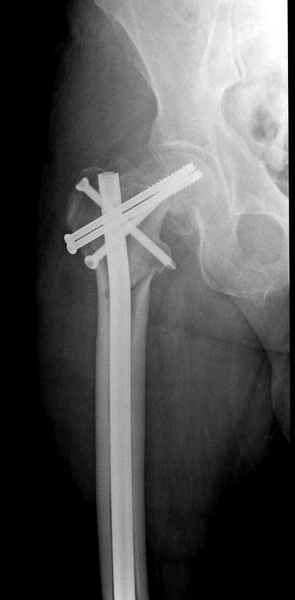

Правильно, ситуация изменилась, как говорят у нас теперь "different animal", надо решать проблему подвертельного перелома. При наличии различных вариантов фиксаторов, включая Страйкер Гамма 3, мы выбрали DePuy Antegrade Trachanteric Nail из-за многовариантности проксимальной фиксации и двойного изгиба. Вводится через вертел под 8 градусным углом, и есть достаточный передний диафизарный изгиб, предупреждающий пенетрацию дистального переднего кортекса.